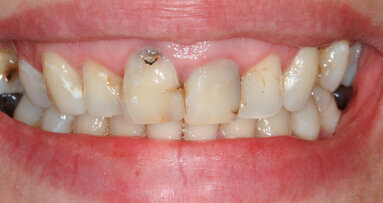

In questo articolo presentiamo un caso clinico che dimostra come il posizionamento improprio di un impianto può rendere impossibile la riabilitazione protesica, che richiede una nuova pianificazione chirurgica e riabilitativa per ottenere l’estetica desiderata. La paziente si presenta alla nostra osservazione con una riabilitazione protesica incongrua, con flangia in resina, a supporto dentale ed implantare, con la presenza di un impianto in posizione 2.1 vestibolarizzato e con l’emergenza nel fornice, in mucosa alveolare. Dalla valutazione della Tac si evince la posizione errata dell’impianto e la perdita consistente in senso trasversale della compagine ossea (Figg. 1, 2). Pertanto si opta per il seguente piano di trattamento che prevede: rimozione dell’impianto e preparazione protesica dell’elemento 2.3, confezionamento di un primo provvisorio a supporto dentale che servirà a guidare la guarigione dei tessuti (Figg. 3-7). A distanza di 4 mesi si procede a un innesto epitelio connettivale libero con prelievo dal palato per compensare il gap dei tessuti molli in senso trasversale, quindi viene ribasato il provvisorio in modo tale da favorire la guarigione dei tessuti (Figg. 8-11). A 9 mesi dalla maturazione dei tessuti si procede alla finalizzazione protesica fissa a supporto dentale (Figg. 12-14).

Fig. 1 - Situazione clinica iniziale.

Fig. 3 - Rimozione del manufatto protesico che evidenzia la posizione errata dell’impianto in sede 2.1.